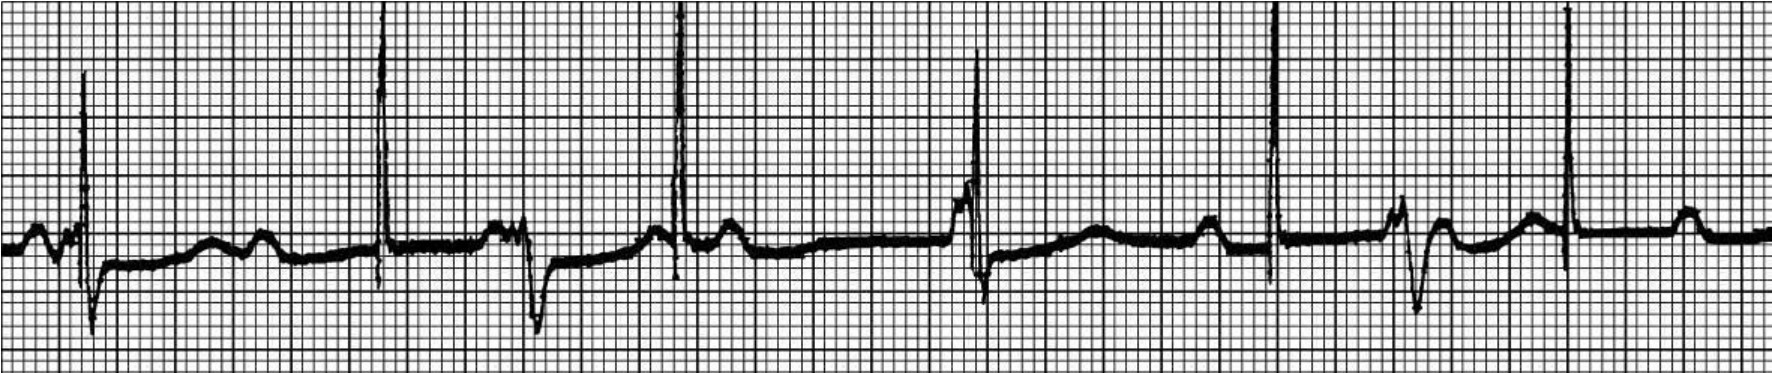

图61-142 室房逆传伴反复心律

图61-143 心房回搏和反复搏动

心室起搏后均出现逆行P波,并再次下传夺获心室,形成反复搏动二联律